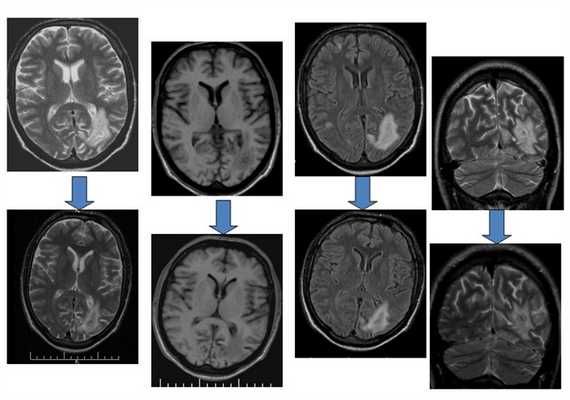

Пациент Н., 30 лет.

Динамика МРТ картины от 22.08.2008 к 12.11.2008![Поражение головного мозга при ВИЧ инфекции]()

![Поражение головного мозга при ВИЧ инфекции]()

Пациентка П.

Тяжелый токсоплазмоз+ВИЧ (летальный исход через 3 дня после исследования)Прогрессирующая мультифокальная лейкоэнцефалопатия